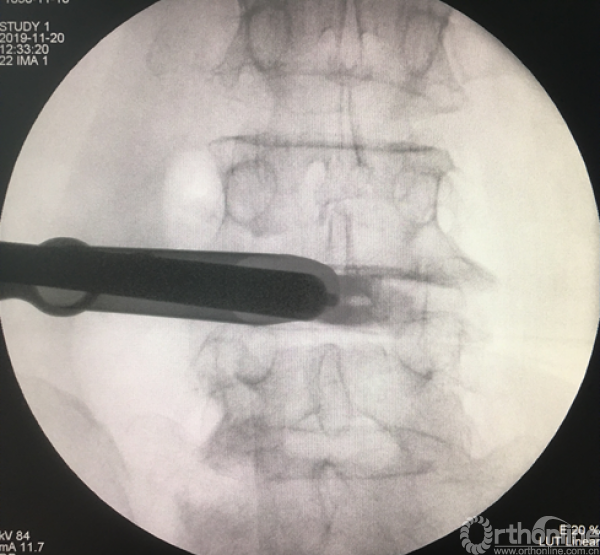

放入工作套管

正侧位透视确定责任节段